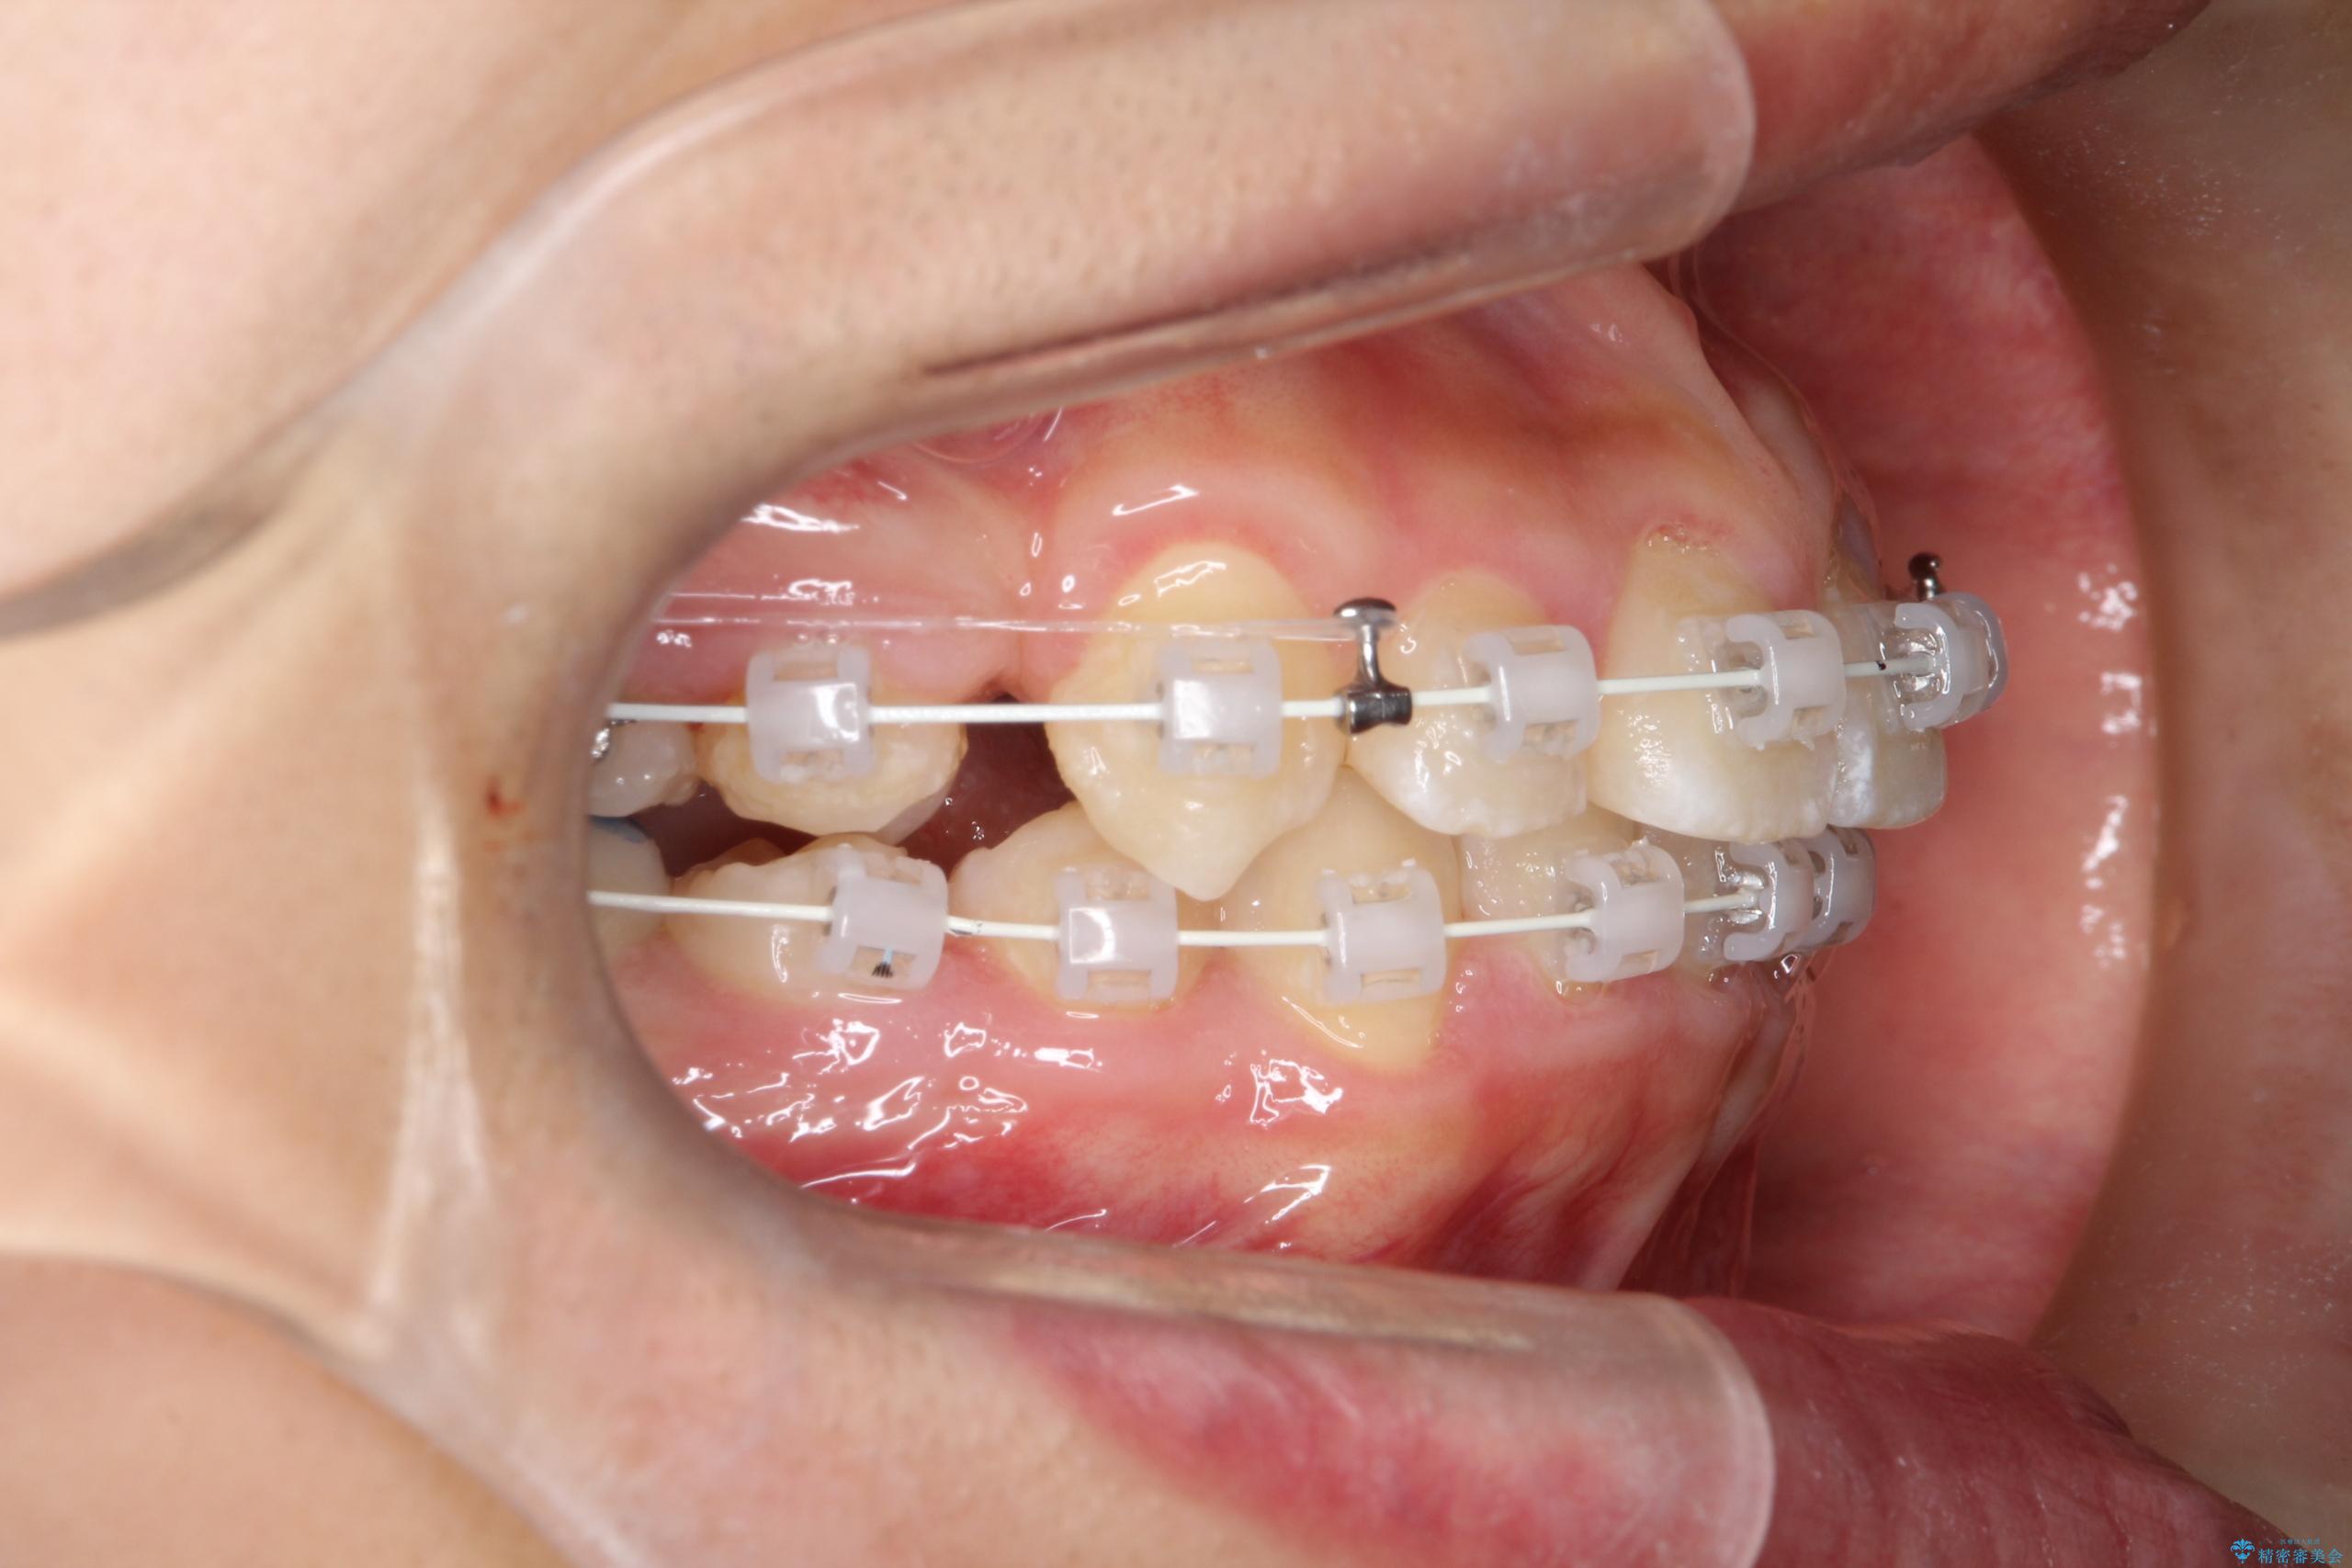

- ワイヤー(審美装置)

矯正の精密検査の結果上顎左右4番の計2本を抜歯し、審美性に配慮したワイヤー矯正装置(審美装置)を用いて治療を行いました。

八重歯などの歯列のデコボコが綺麗に改善され、患者様にも大変喜んでいただけました。また、咬み合わせが深い「ディープバイト」も併せて改善し、見た目だけでなく機能面でもバランスの取れた咬合を獲得しています。